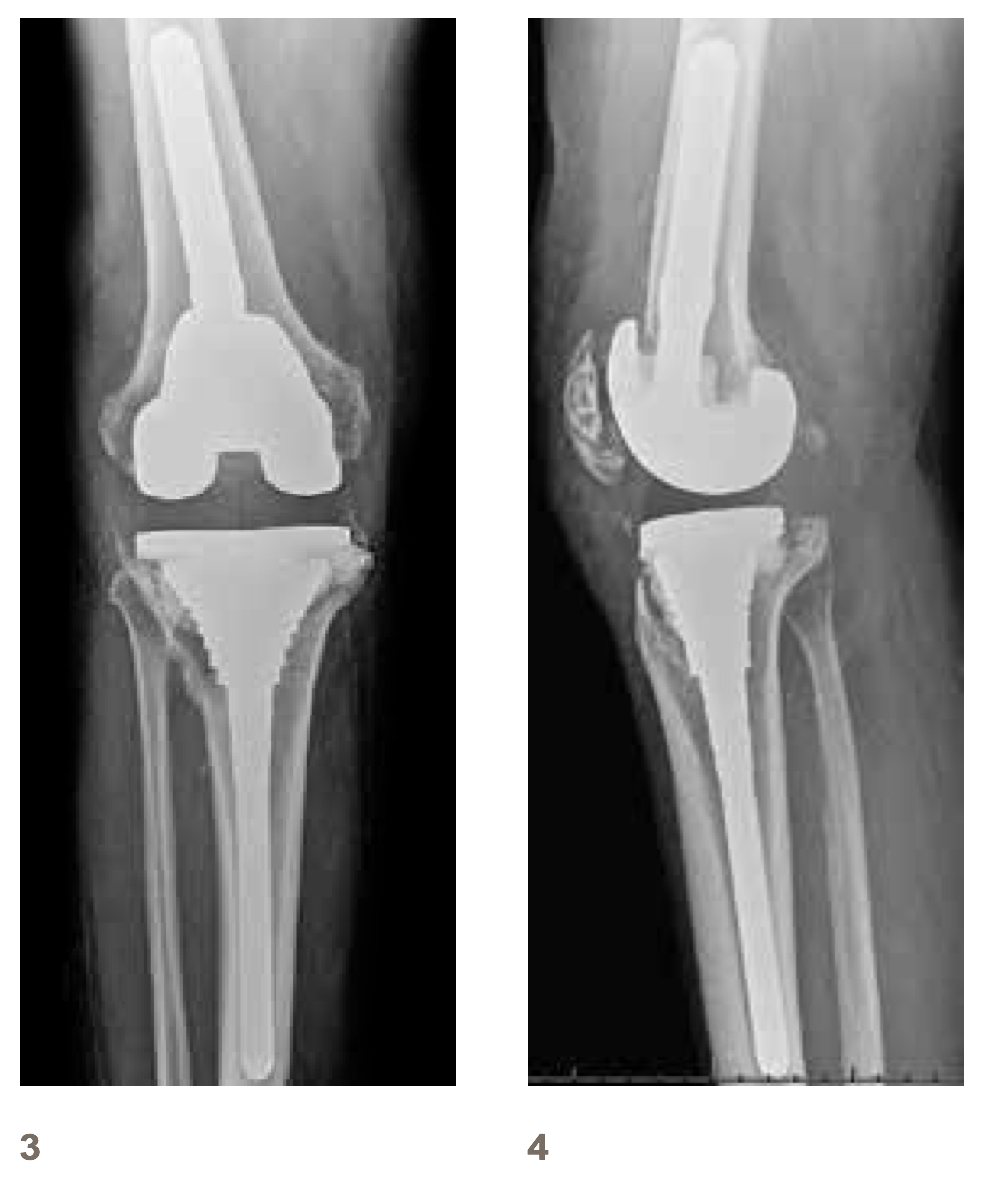

X-rays after changing to a revision prothesis

1 Right knee front view

2 Right knee lateral view